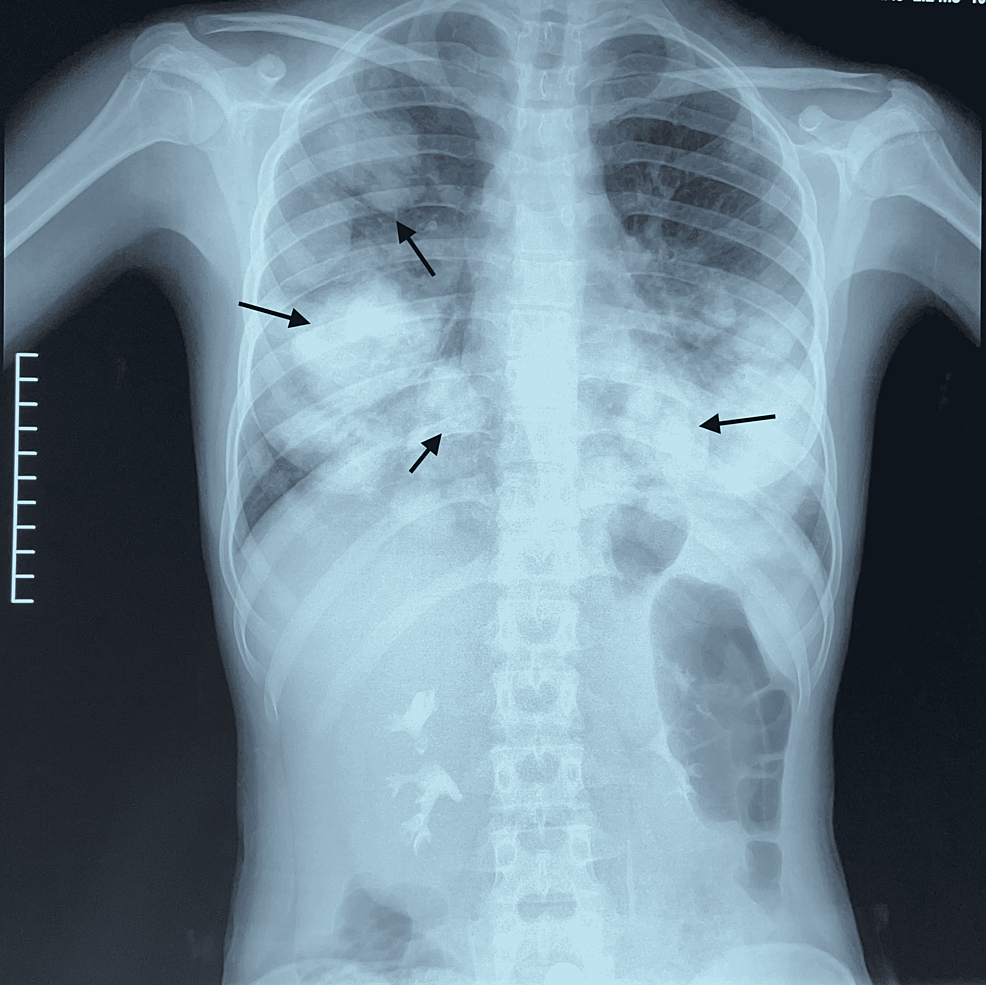

Plain chest Xray showing “cannonball” lesions. Download Scientific Cannon Balls X Ray — larger nodules and masses may be termed cannonball metastases. Atypical features include consolidation ,. The most obvious finding is that of numerous bilateral round hyperdensities of variable sizes of the pulmonary. Cannon Balls X Ray.

Cannon Balls X Ray . Atypical features include consolidation ,. The most obvious finding is that of numerous bilateral round hyperdensities of variable sizes of the pulmonary. — larger nodules and masses may be termed cannonball metastases.

Atypical features include consolidation ,. — larger nodules and masses may be termed cannonball metastases. The most obvious finding is that of numerous bilateral round hyperdensities of variable sizes of the pulmonary.